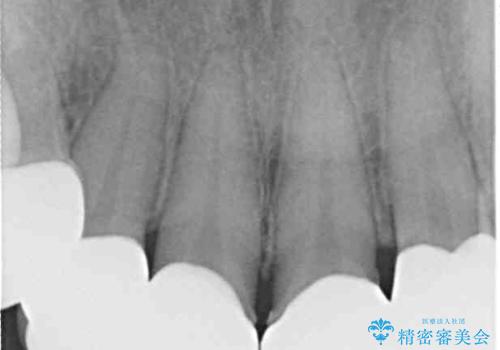

- 長年前歯の歯並びで悩んでいるとのことで来院された患者様です。

機能的なことを考えると八重歯となっている犬歯は抜歯せず、歯列を改善することが望ましいとされますが、数十年もの間犬歯がない咬み合わせで問題なく過ごしてきたため、八重歯を抜歯することで、手っ取り早く歯列を改善することとしました。

また、当初は予定しておりませんでしたが、歯列が整ったことで前歯の歯の色や形が気になり、矯正治療後にオールセラミッククラウンにて補綴治療することとしました。